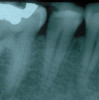

Chronic apical abscess: Radiography typically reveals a radiolucency. Clinically, there is a sinus tract present on the gingival tissue. The draining sinus tract should be traced with a gutta-percha cone and then confirmed radiographically (Figure 5 and Figure 6).

Fig 5. Clinical confirmation of the periradicular diagnosis—chronic apical abscess on tooth No. 19. The tooth is not sensitive to percussion or palpation. A gutta-percha cone is inserted into the sinus tract.

Figure 5

Fig 6. Radiographic confirmation of periradicular diagnosis—chronic apical on tooth No. 19. Note the tracing of the inserted gutta-percha to the etiology. Local anesthesia is generally not required for a sinus tract tracing.

Figure 6